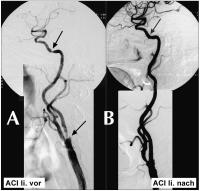

Abbildung 1A-B: A) Hochgradige symptomatische Stenose der A. carotis interna; B) gutes morphologisches Ergebnis nach erfolgreicher Stentangioplastie